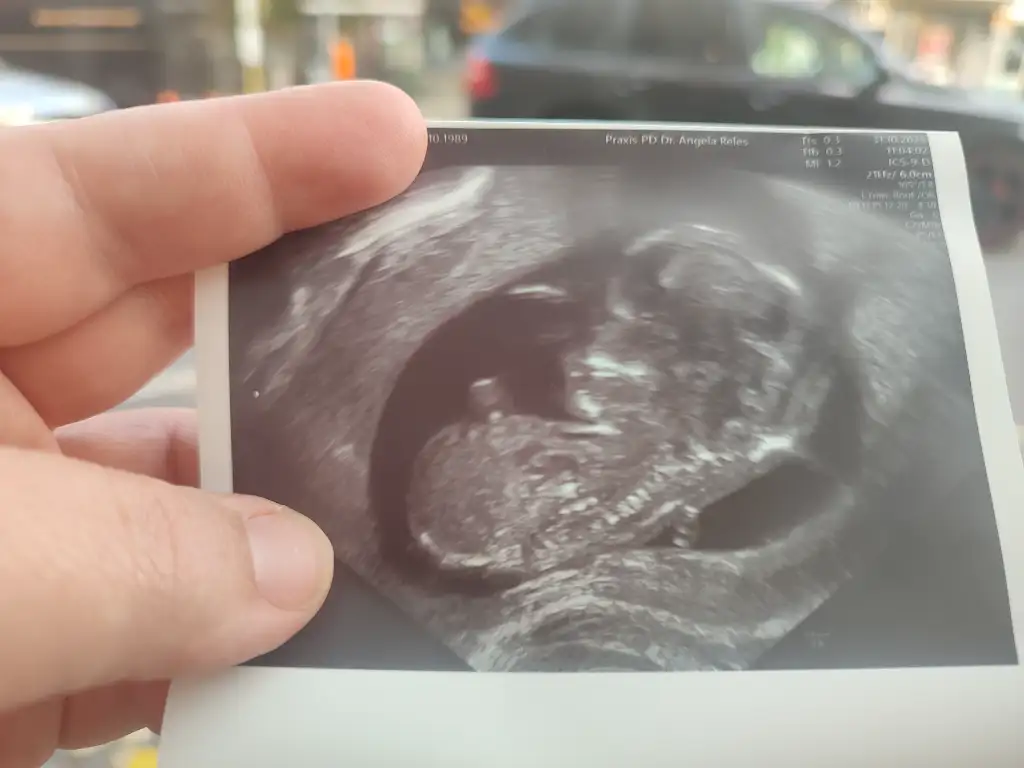

Benim 12.haftamda cinsiyetini söyledi doktor. Bu şekilde görünüyordu.12 haftalık

Kız mı sizinBenim 12.haftamda cinsiyetini söyledi doktor. Bu şekilde görünüyordu.